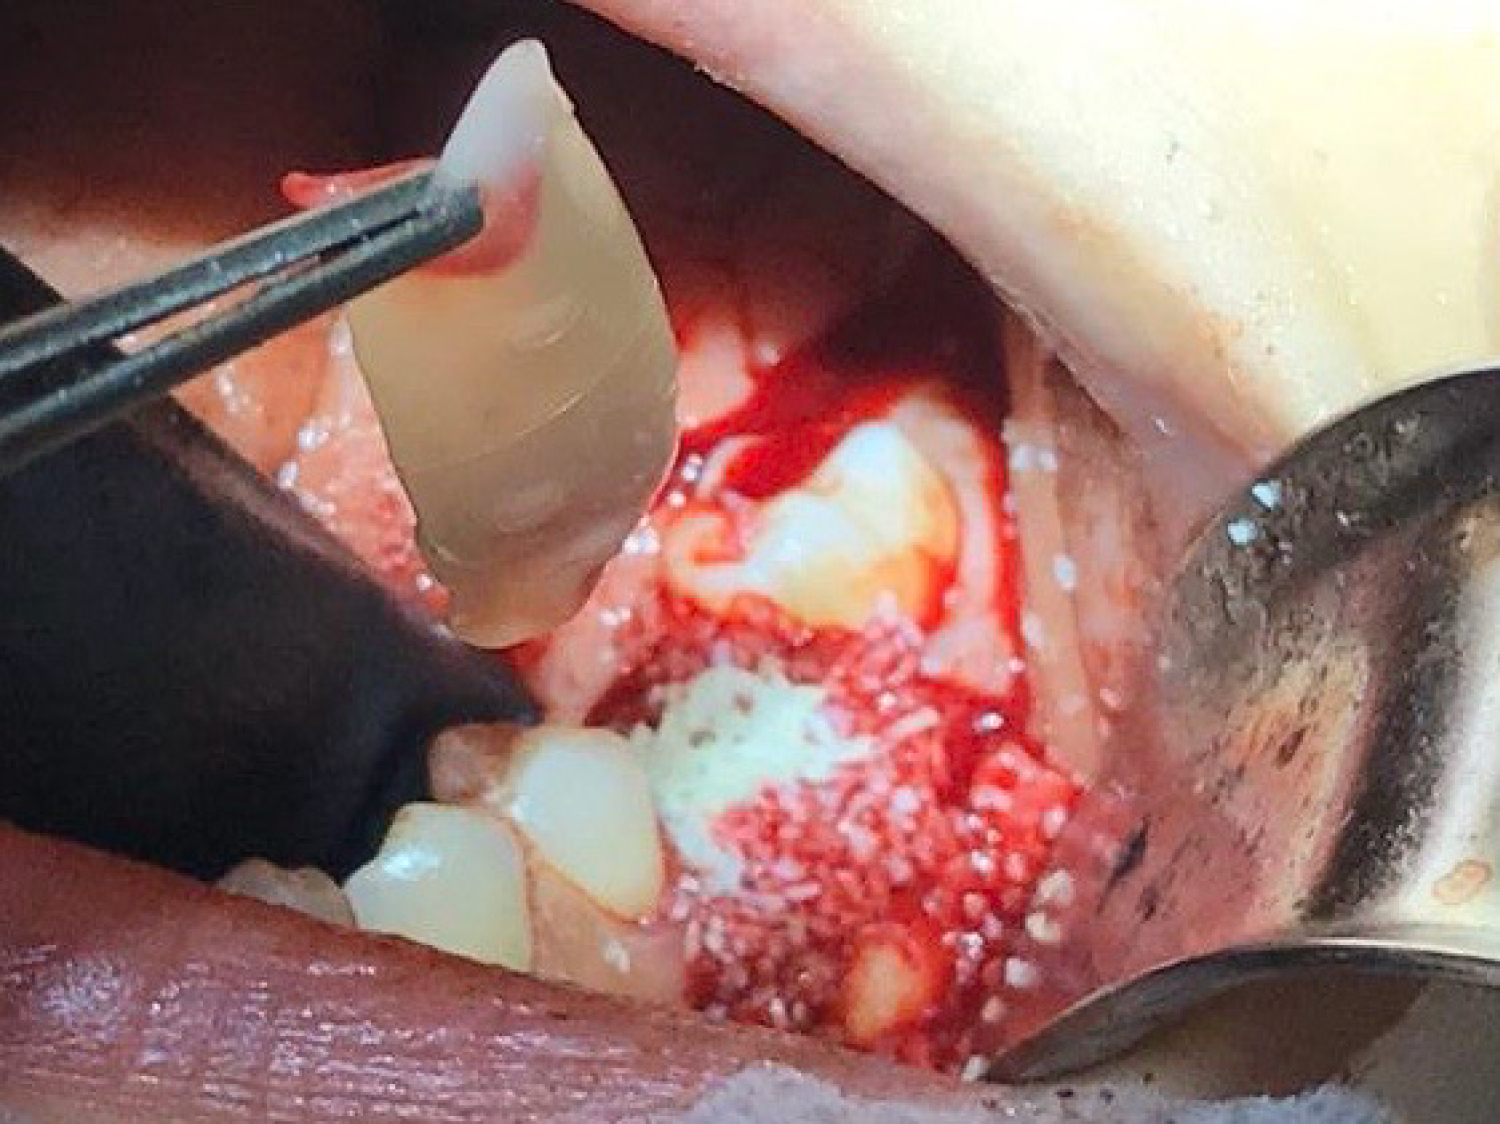

A 29-year-old female patient attended the Oral and Maxillofacial Surgery Unit of University Hospital of Maracaibo, Venezuela, presenting pain in the posterior left mandibular region. Her medical record was unremarkable. On clinical examination, the inferior left first molar (#36) presented with endodontic treatment which had been performed in two previous opportunities due to the persistence of associated pain on vertical and transversal percussion. A panoramic X-ray was requested, and the endodontic treatment with a partially fractured crown was observed in the aforementioned tooth, with no radiolucent images associated (Figure 1). Due to these findings, the final diagnosis of cracked tooth syndrome was decided and thus, the treatment plan chosen was to extract the tooth and place an implant using a surgical guide in the same surgery along with guided bone regeneration. The patient's mandibular cast was scanned using an extraoral scanner (Ceramill Map 300, Amann Girrbach, Austria) (Figure 2) and the STL file was obtained and edited in order to eliminate the crown of the tooth using MeshMixer program (Autodesk, Canada) (Figure 3). The edited denture scan was aligned to the mandibular CBCT scan of the patient in Blue Sky Plan (Blue Sky Bio, USA) to allow for prosthetically driven implant planning. Implant placement simulation was carried out in the software aiming for the site with the most surrounding bone while being prosthetically acceptable (Figure 4) and a surgical guide was designed and printed in a desktop 3D printer (AnyCubic Photon, China) (Figure 5 and Figure 6). Under moderate sedation and local anesthesia, the molar was a traumatically extracted, the surgical guide was held in position (Figure 7) and a 4.0 × 13 mm IS II active implant (NeoBiotech, Korea) was placed using the NeoBiotech Naviguide system. Subsequently, the alveolar gaps were filled using cortico-cancellous bone allograft (Ossogen, Lattice Biologics, USA) (Figure 8) and two Platelet-Rich Fibrin (PRF) membranes made using the protocol described by Choukroun [6] (Figure 9). Simple sutures using 3-0 polyglactin 910 (Vicryl, Ethicon, USA) were used for closure.

Figure 8: Use of cortico-cancellous bone allograft to fill the gaps of the socket. View Figure 8